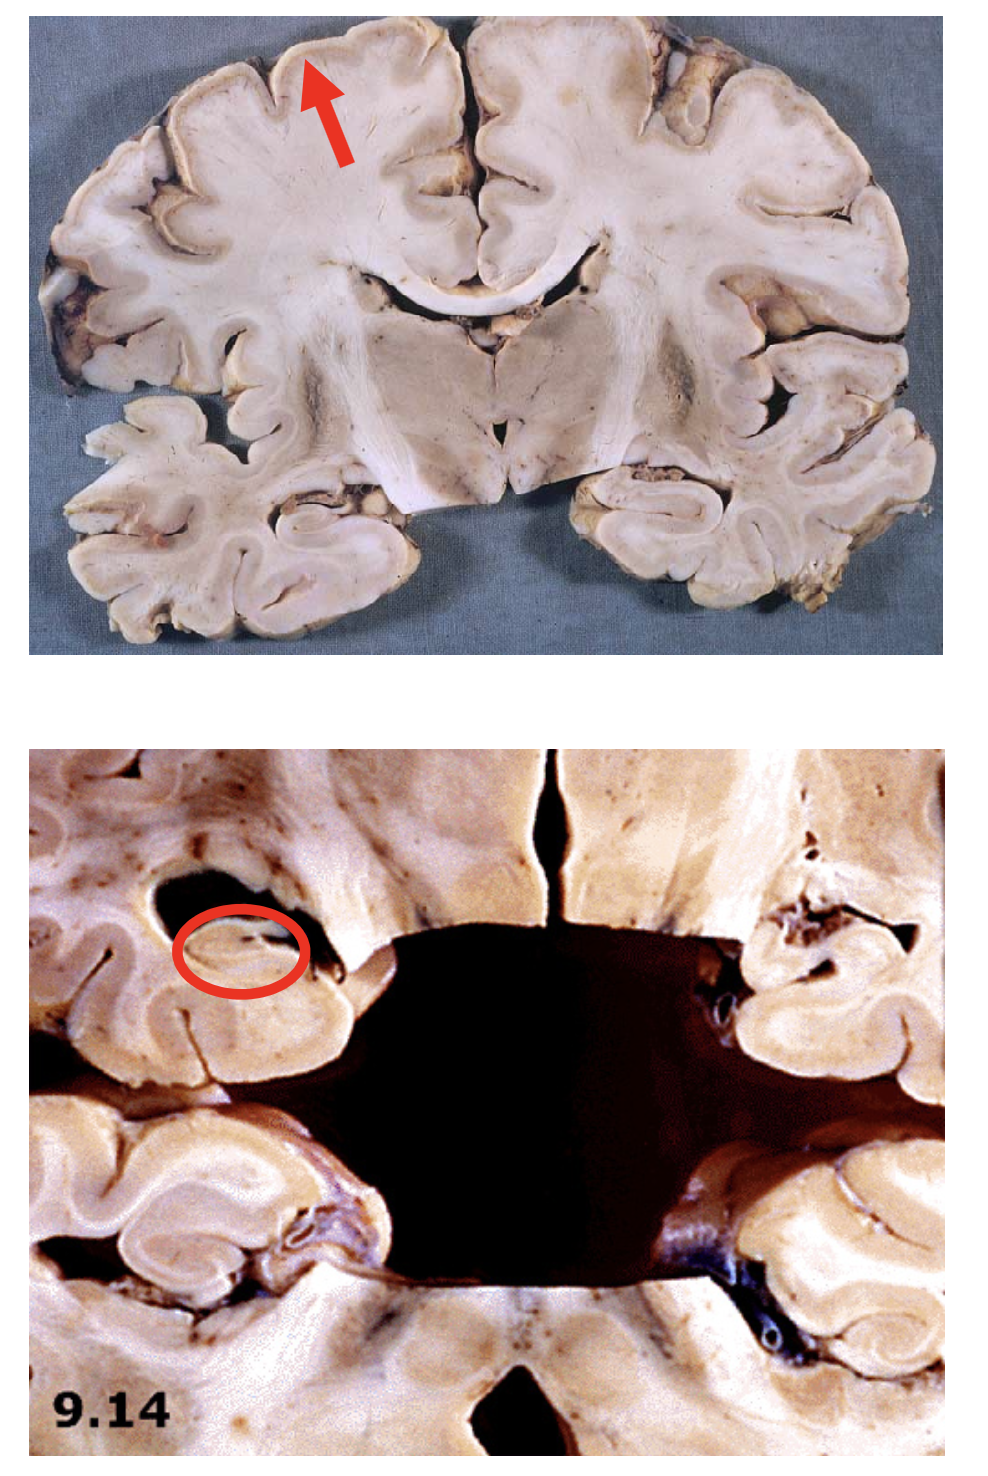

Chronic cortical ischemic stroke

Aftermonths,allthat remains is a cystic cavity surrounded by gliotic tissue with glial strands (circle)

-There is compensatory (ex- vacuo) ventricular enlargement (open arrow)

Wallerian degeneration of the cerebral peduncle and corticospinal tract in the pons. (arrows)